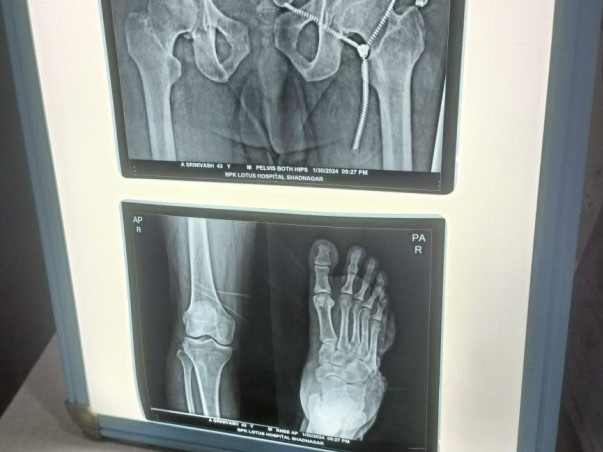

However, srinivas is now facing a significant challenge in his own life. He has been diagnosed with an accident followed by right hand spine and right leg damage and his treatment requires immediate and substantial medical intervention. The cost of treatment is overwhelming, and despite his immense contributions to society, he finds himself in need of help at this critical juncture.

I met with a road accident and have been suffering from a severe spine and leg injury for the past few months. The doctors have advised me to undergo spine and leg surgery, but I have been confined to bed rest since the accident. I am receiving medication at Lotus Hospital in Shadnagar, Telangana, but I have not yet been admitted due to a lack of funds.